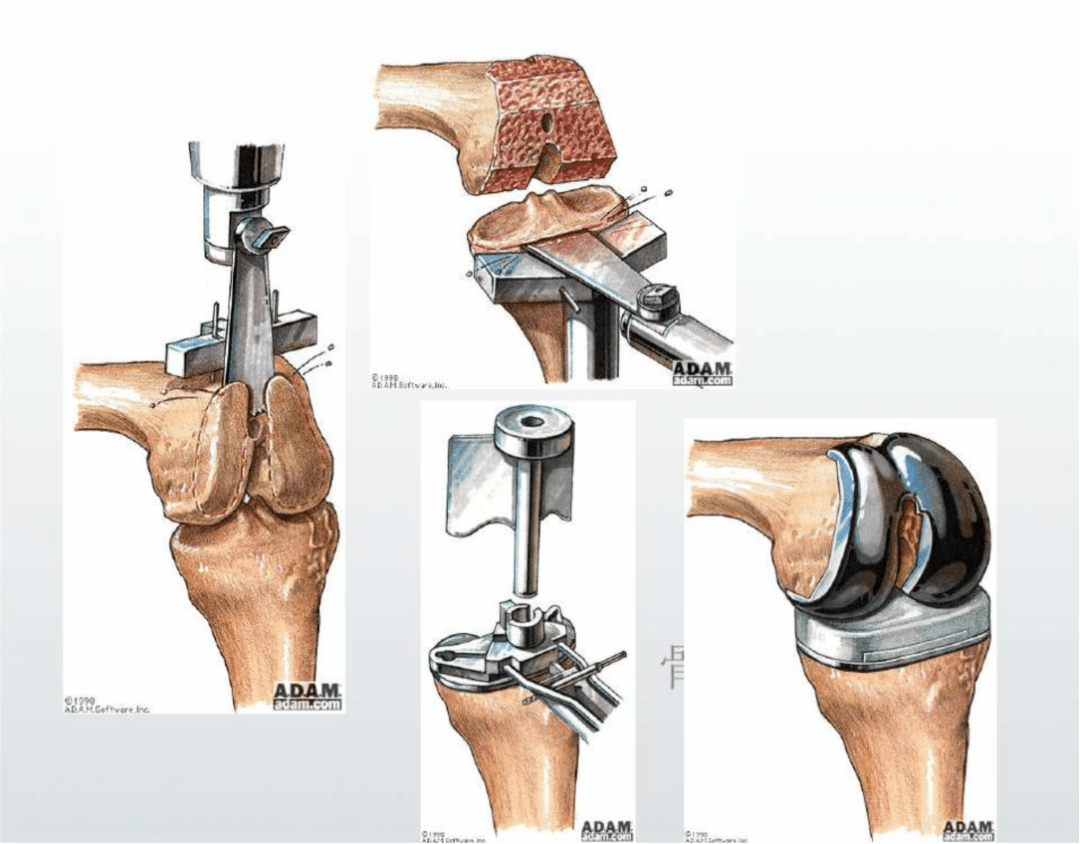

人工膝關(guān)節(jié)置換:是在近代人工髖關(guān)節(jié)成功應(yīng)用于病人后逐漸發(fā)展起來(lái)的一種治療膝關(guān)節(jié)疾病的新技術(shù),是治療嚴(yán)重膝骨關(guān)節(jié)病的切實(shí)有效方法,它能非常有效地根除晚期膝關(guān)節(jié)病痛,極大地提高病人的生活質(zhì)量,在發(fā)達(dá)國(guó)家比較流行。膝關(guān)節(jié)置換就是切除膝關(guān)節(jié)軟骨損壞的表面,并安置一個(gè)人工表面和墊片,構(gòu)成一個(gè)新的關(guān)節(jié),該手術(shù)可以減少患者的疼痛,糾正患者膝關(guān)節(jié)的畸形,恢復(fù)患者膝關(guān)節(jié)的屈伸活動(dòng)。